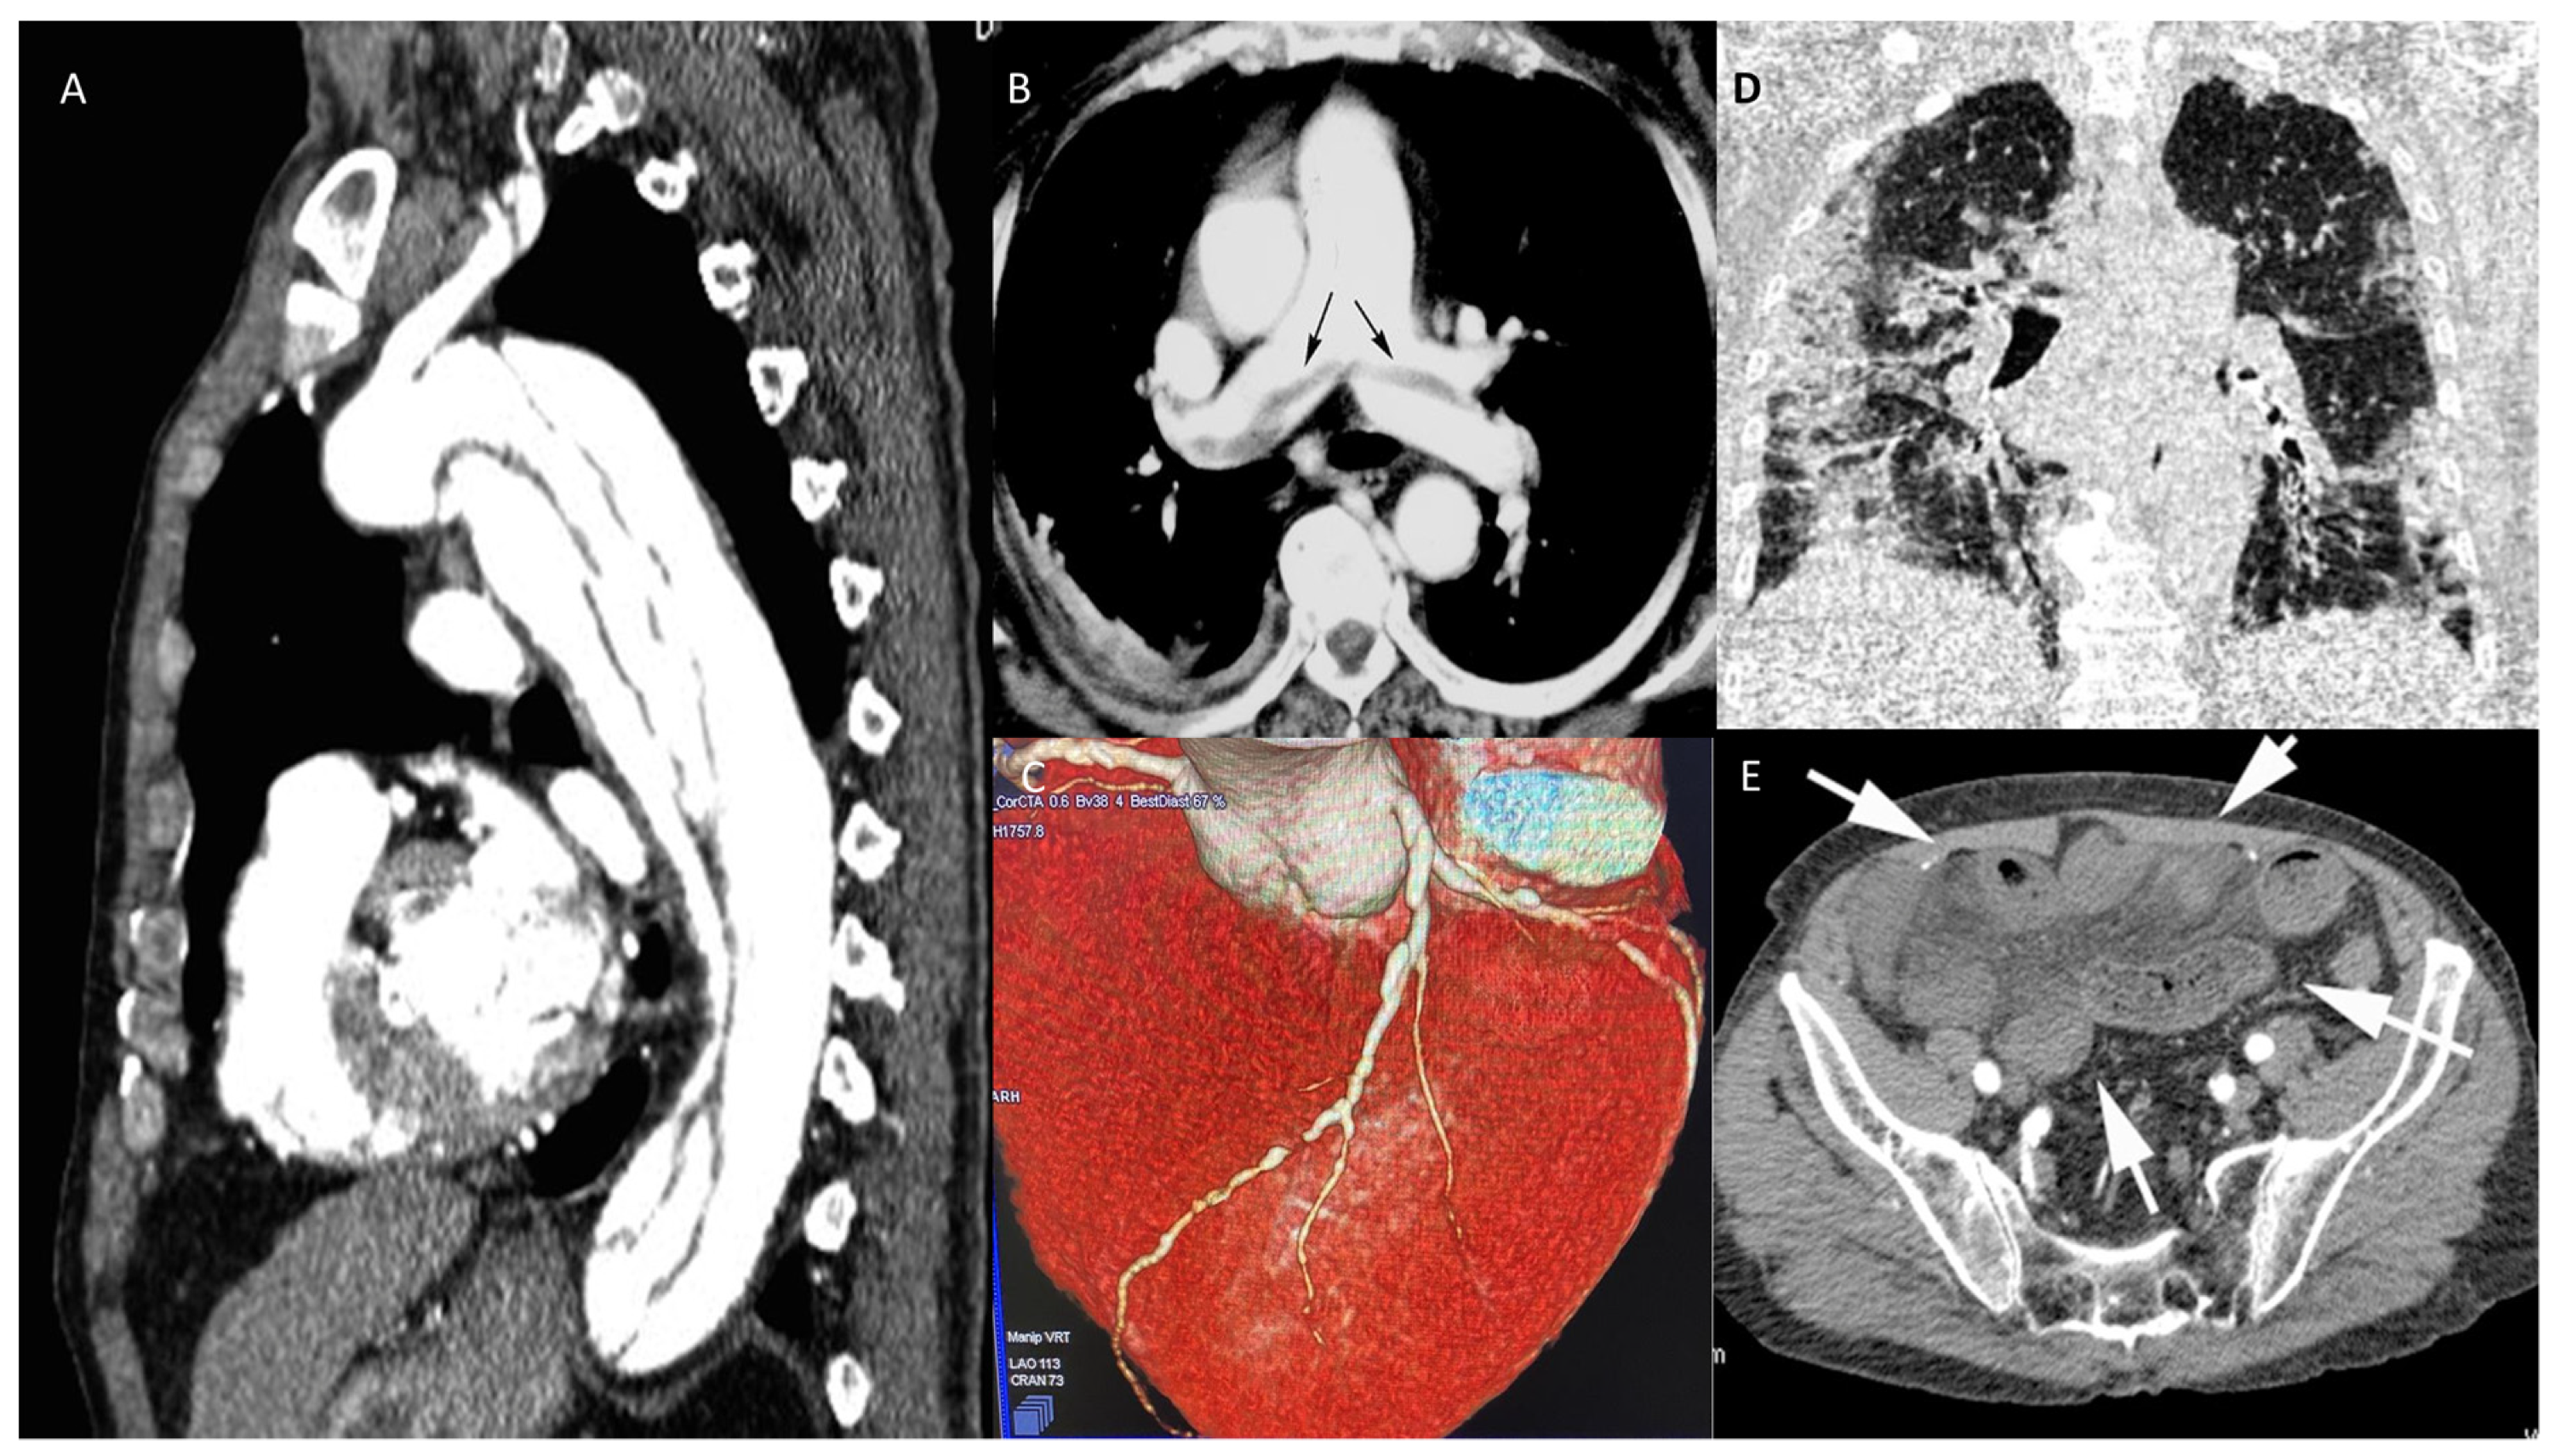

- High-resolution chest computed tomography (Chest HR-CT)

- Chest CT angiography (CTA)

- Coronary angiography